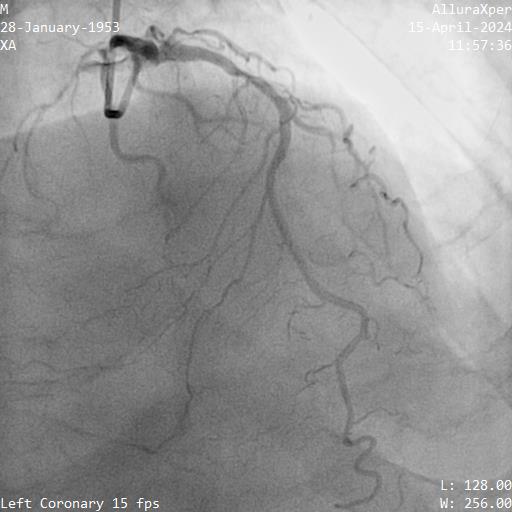

Relevant Catheterization Findings

1. LMT was normal

2. Proximal LAD had a 70-80% stenosis, mid LAD had myocardial bridging. LAD supplied septal collateral (CC) to distal PDA

3. Proximal LCX artery had a 90% stenosis

4. Proximal RCA was diffuse disease 70-80%, mid to distal RCA was a CTO. Ipsilateral CC from marginal to PDA

Interventional Management

Right femoral and right radial arteries were punctured. A 7Fr EBU 3.5 guiding catheter (GC) was used to engage LMT. A 7Fr JR 4 GC was used for RCA CTO PCI. For antegrade preparation, a wire was delivered into right marginal artery. For antegrade proximal cap puncture, a Finecross microcatheter (MC) and Fielder XTR was used to wire into mid RCA CTO, but XTR fail to advance further. For retrograde approach, a CorsairPro ES (150 cm) MC, SION and SUOH 03 wire were used for LAD septal wiring but failed. A Sion Black with 90 degree tip successfully negotiate the collateral and entered PDA. The distal cap was hard to puncture. UB3 was used to puncture the distal cap and managed to cross and externalized into antegrade GC. Attempt was made to advance retrograde MC but failed at the point of PDA/PLV bifurcation.

Next plan was using retrograde UB3 to tip in antegrade MC successfully. However, the antegrade MC crossed the CTO body but failed cross PDA despite anchoring balloon at marginal artery. Next, switched to antegrade, escalated the antegrade wire to GAIA Next2 and using retrograde wire as a marker to facilitate antegrade wiring. Fortunately, the GAIA Next 2 managed to entered PLV. IVUS confirmed wire in true lumen after predilatation. The PDA was wired using CRUSADE MC to keep wire access for PDA and PLV.Distal RCA-PDA stented with everolimus eluting stent (EES) 2.5x32mm, mid RCA EES 3.5x32mm, and ostial RCA EES 4.0x24mm, post dilated NC 3.0x15mm, and 4.0x15mm balloon.